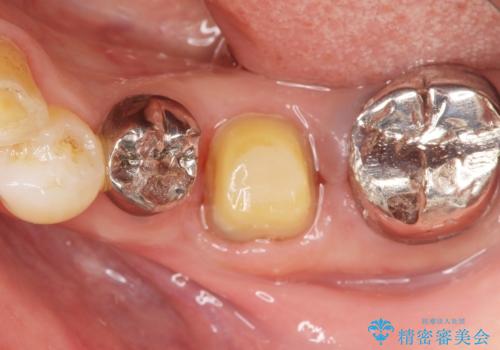

精査したところ奥歯(左下6)が破折しており、保存不可能と診断されました。

保存不可能な奥歯(左下6)を抜歯し、機能していない親知らず(左下8)の移植を行いました。

移植後、生着を待って根管治療及び補綴修復を行いました。